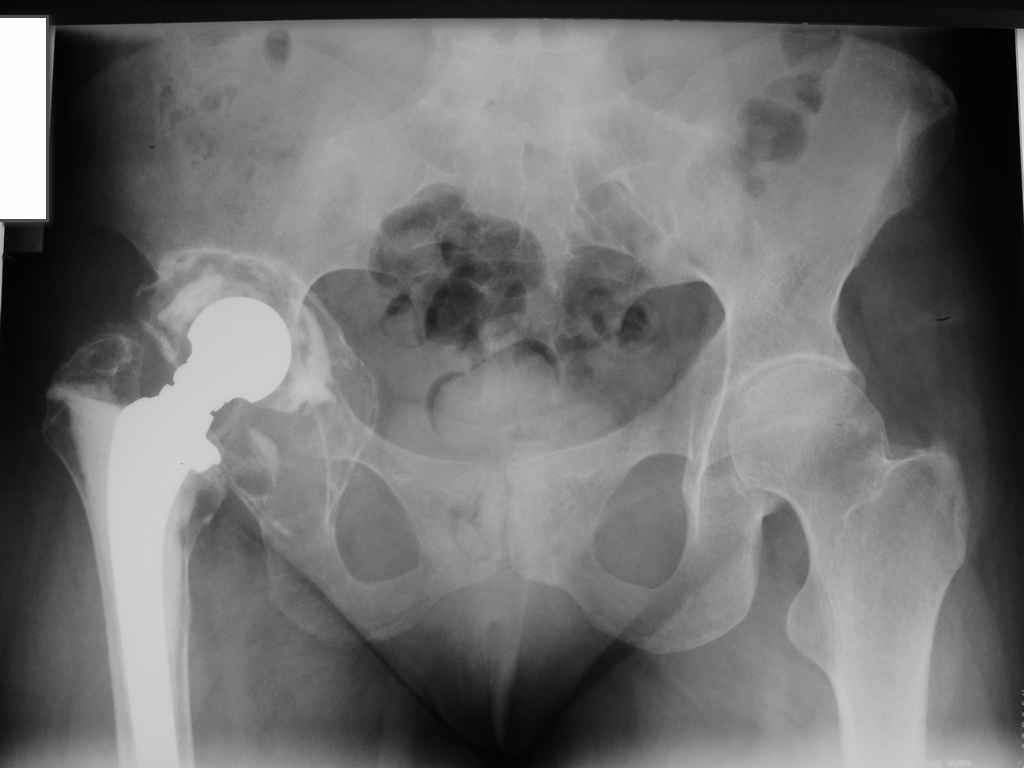

Больная 40 лет, поступила в отделение с диагнозом: Нестабильность чашки цементного эндопротеза Мовшовича правого тазобедренного сустава с протрузией тазового компонента.

Рентгенограммы от 07,07,2009г.

Помогите определиться с выбором оптимального варианта ревизии:

Планируем использовать кольцо Бурх—Шнайдера большого размера 60 (внутренний диаметр) и аллотрансплантат для пластики дна впадины и тела седалищной кости, чтобы получить возможность фиксации нижней клиновидной части кольца и уменьшить размер дефекта.

пластика вертлужной впадины массивным аллотрансплантатом с установкой в него цементной чашки.